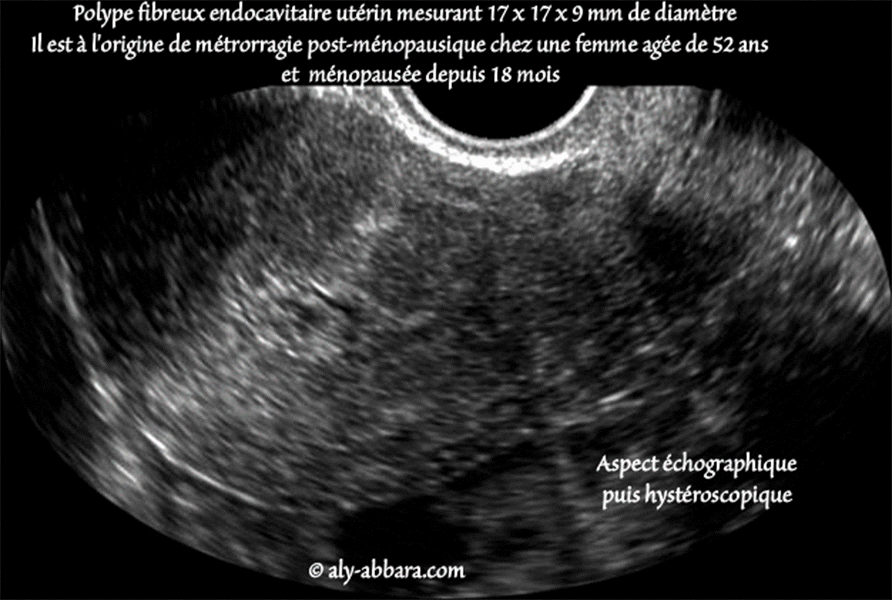

| Polype fibreux endocavitaire de l'utérus (Auto-diaporama composé d'une deux images échographiques de l'utérus, la première est sagittale médiane et la deuxième est transversale, au niveau du fond utérin, et enfin, une image hystéroscopique montrant l'aspect macroscopique de ce polype à pédicule large, et qui s'est développé sur la paroi latérale gauche du corps utérin, au niveau de la jonction du tiers moyen et le tiers supérieur en occupant le fond de la cavité utérine. On constate facilement l'atrophie de l'endomètre sur les images échographiques et dans l'image hystéroscopique) |

Il s'agit d'un polype fibreux bénin mesurant 17 x 17 x 9 mm de diamètre, il fut à l'origine de métrorragie post-ménopausique chez une femme âgée de 52 ans, ménopausée depuis 18 mois. Pour comparer ce polype à un polype muqueux, cliquez ici, et ici, puis ici |